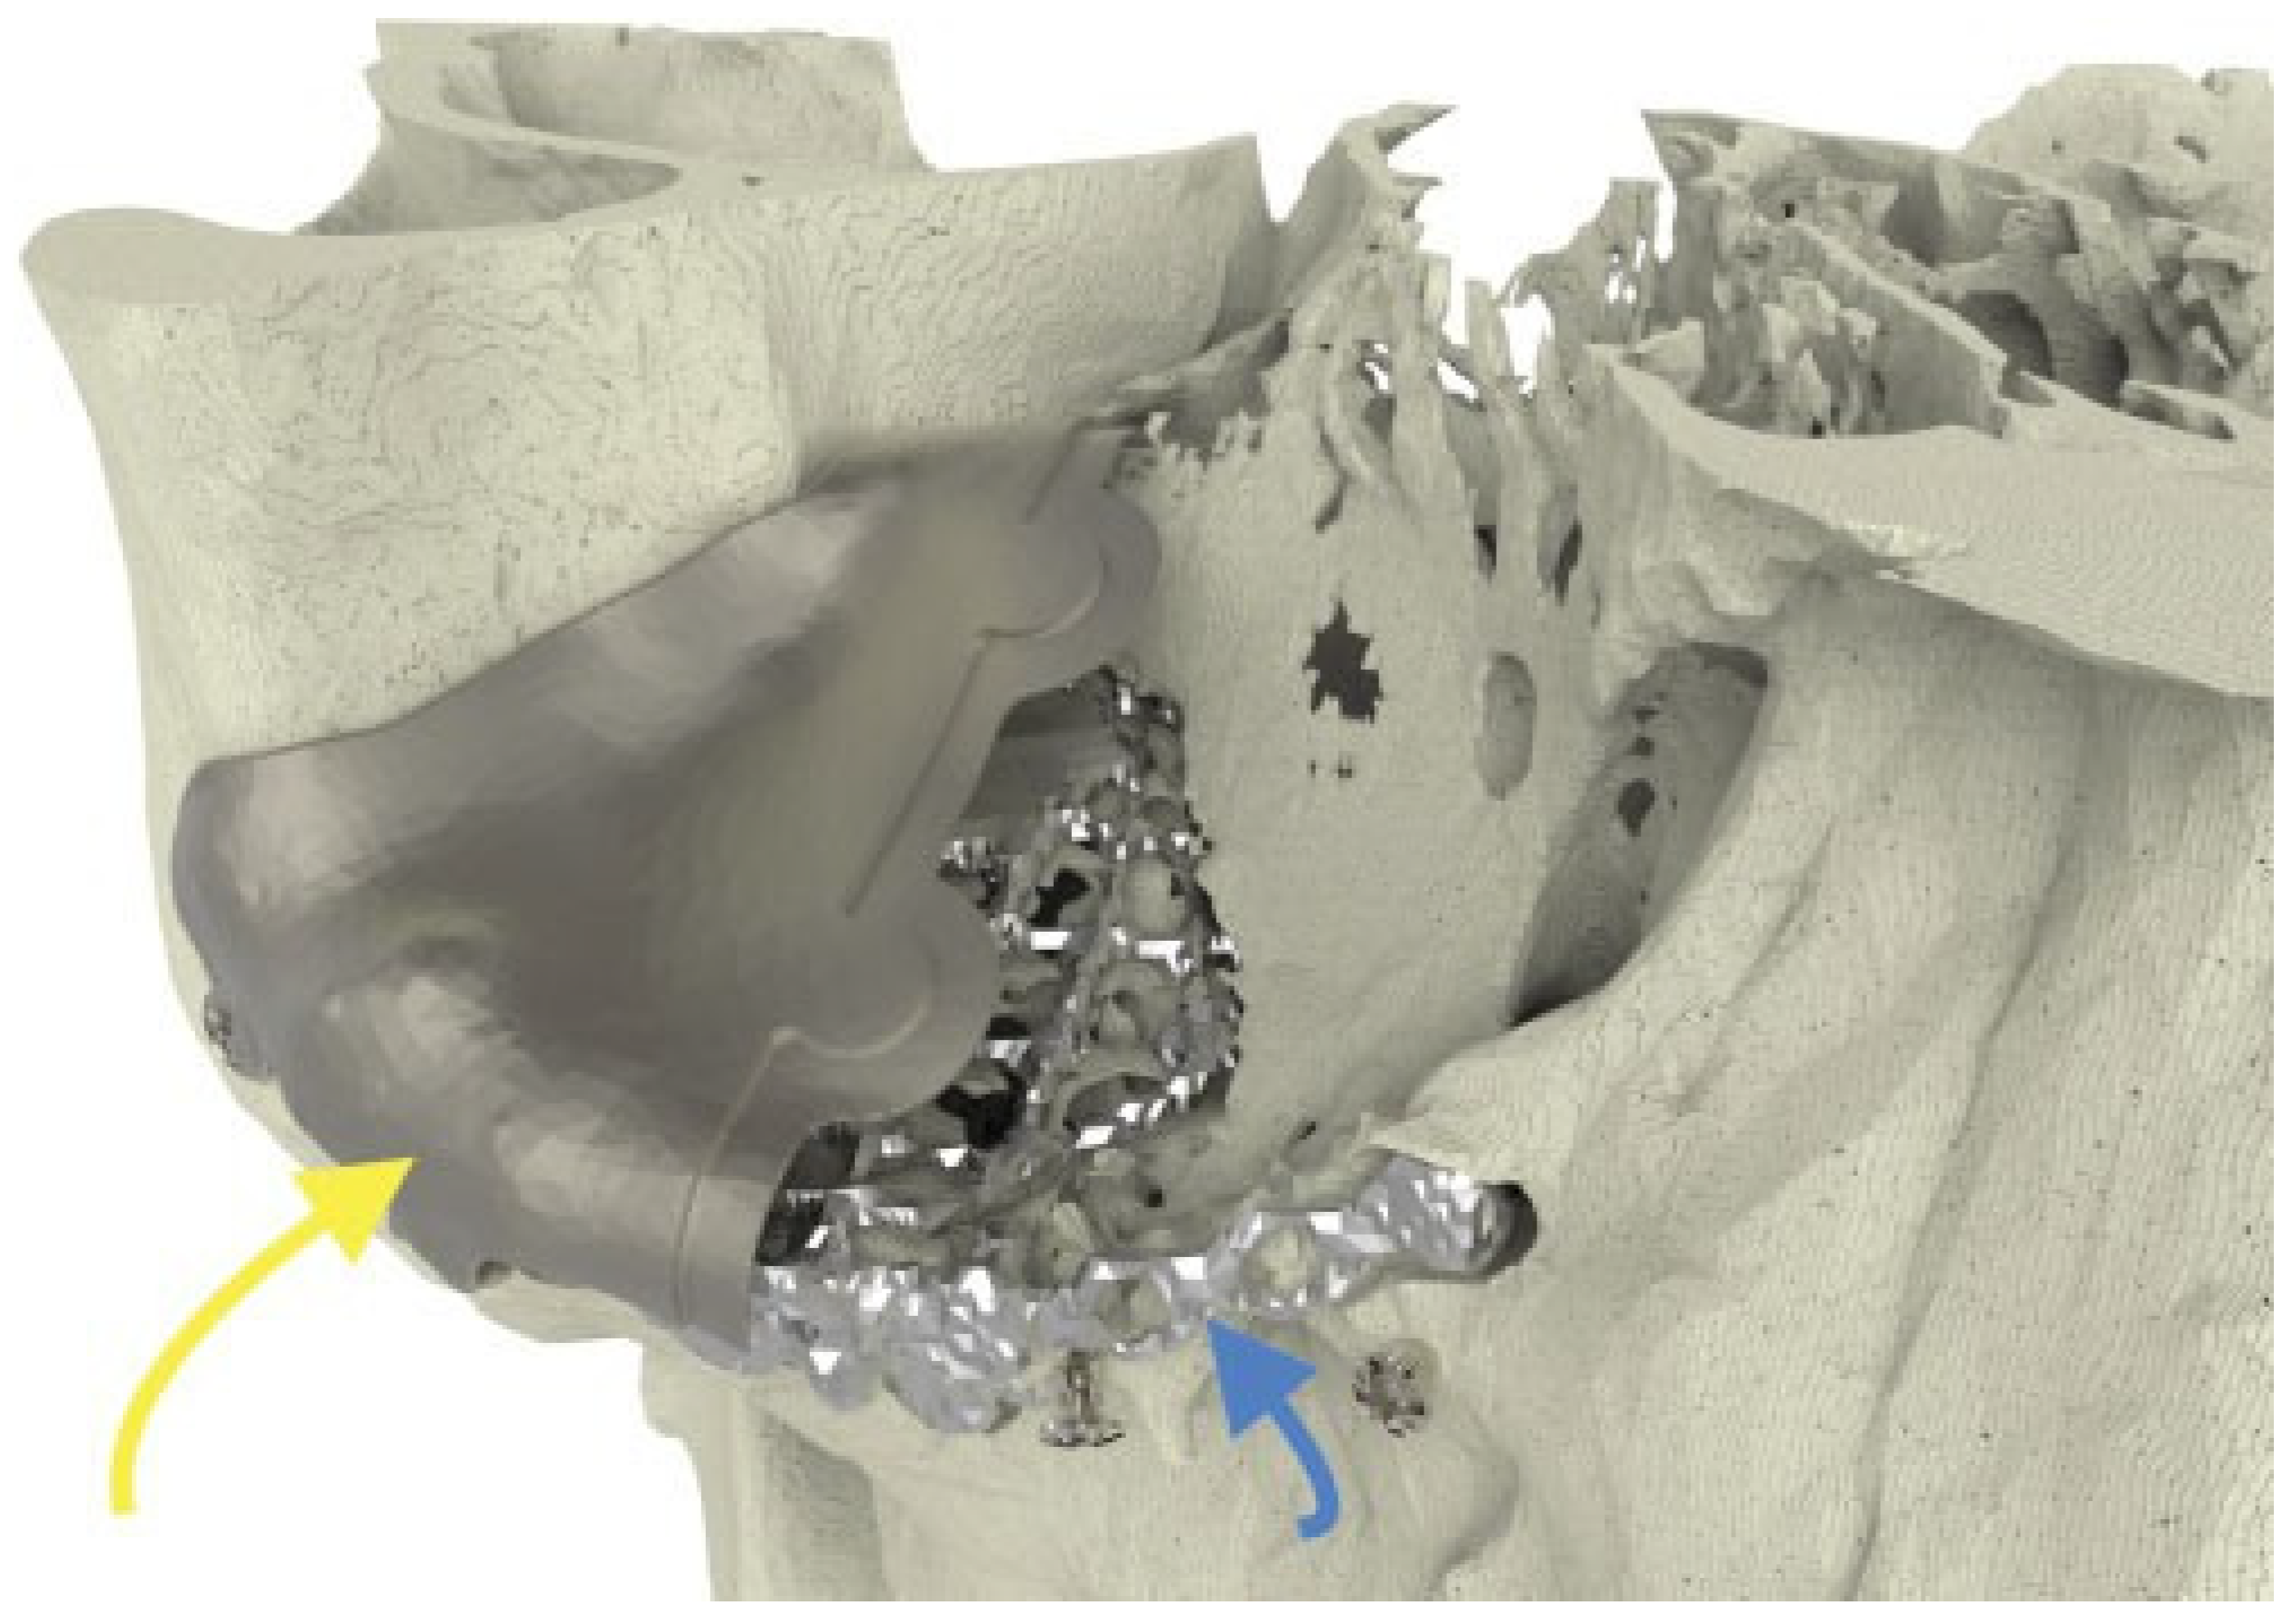

Figure 1. Case 3: The two-piece puzzle design with overlap at the rim. Positions of implant screw holes took into account the underlying structures (orbital mesh, infraorbital nerve, lacrimal system). Information regarding the ideal screw length was provided.

A 28-year-old man was referred with disabling diplopia and severe globe malposition after two repairs of an impure orbital floor fracture using a stock titanium orbital mesh plate (►Figure 9). He had been hit by a pulley in a work accident. The presence of the previously inserted titanium mesh slightly hindered implant design because of the scatter effect on CT scan. Mirroring revealed a height difference of 7 mm between the unaffected side and the mesh on the affected side (►Figure 10, Figure 11 and Figure 12). The 3D model had to take into account the lower position of the orbital rim, and the screw position was based on the amount of remaining bone and positions of the mesh, infraorbital canal, and lacrimal system. The porous implants were printed with a double tongue-in-groove design (►Figure 1 and Figure 10). The puzzle-piece design allowed precise fit between the first and second implants (►Figure 12). Anterior flanges were not necessary as the shape of the reconstructed infraorbital rim provided anteroposterior guidance. Slight diplopia in extreme upward gaze and lagophthalmos remained because of previous fibrosis (►Figure 9).

The puzzle-like interlocking of the implant pieces allows unambiguous anteroposterior positioning of one piece relative to the other. Overlapping edges of the connection provide an interlock in the coronal plane, avoiding downward rotation of the connection when manually adapted (►Figure 1).

Our first design did not include the overlap. In the second design, the overlap was added, and screw heads were partially sunk into the implant. In the third design, vertical flanges were added anteriorly to determine depth position; they were removed once the implants were in position. The ability of the implant shape to provide stable support can be determined by overlapping the margins of the reconstructed and the defective orbit. The screw positions must take into account the infraorbital nerve, lacrimal apparatus, bone quantity, and insertion angle.